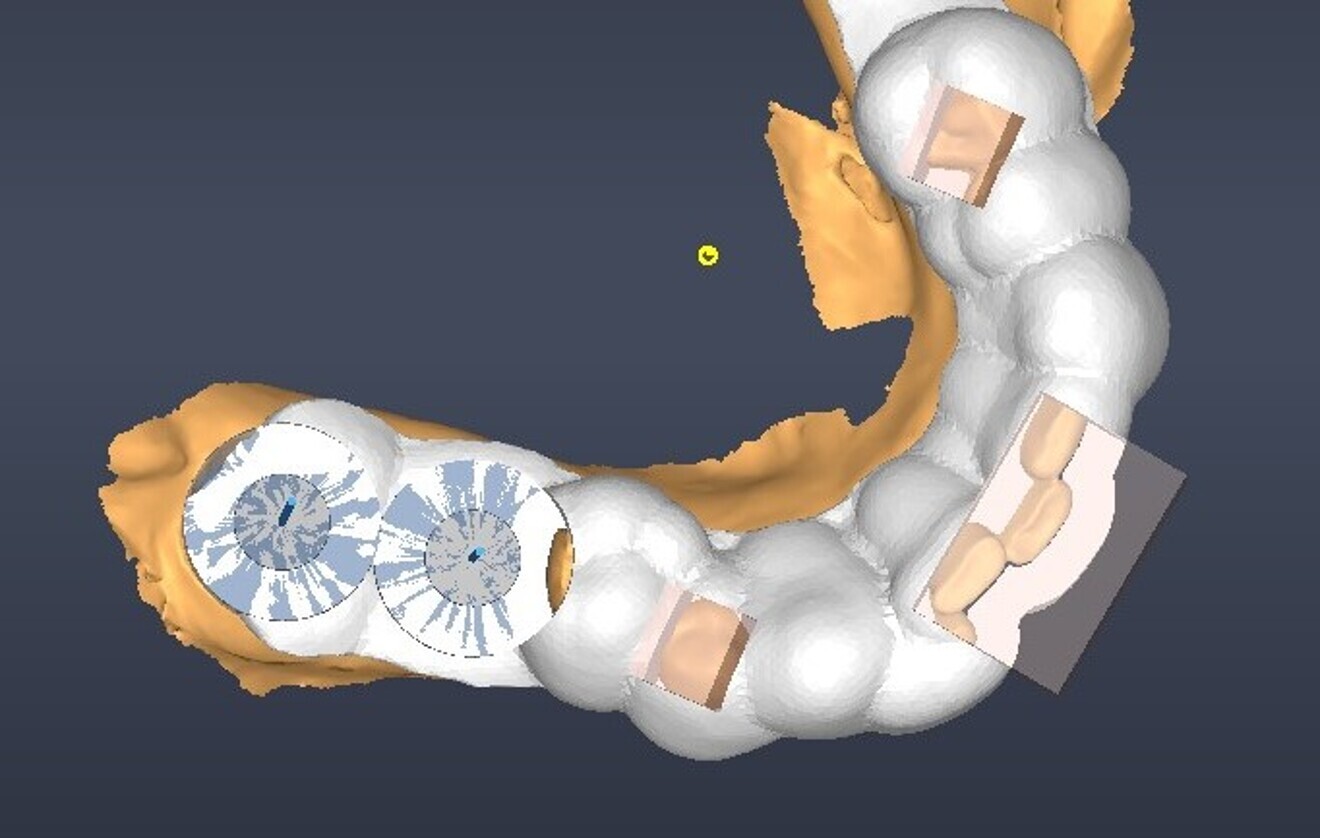

A guided surgical approach was selected, specifically a sleeveless guide, to make use of the precision that it affords in such cases. The DentiqGuide software (3DII) was used to plan treatment in order to establish precise implant positioning. The surgical guide was then printed on a Sonic Mini 8K S (Phrozen), ensuring high accuracy in execution.

Fig. 3: Virtual extraction.

Fig. 4: Digital implant planning, occlusal view.

Fig. 5: Digital implant planning, labial view.

Fig. 6: Surgical guide design.